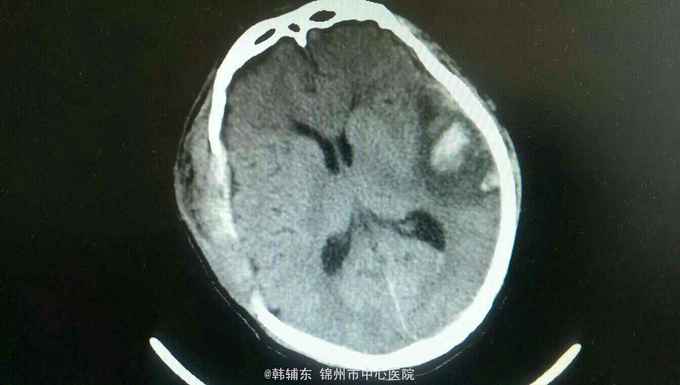

诊断:脑疝 急性硬膜外血肿 脑挫裂伤 颅骨骨折 入院后完善术前准备,急诊行去骨瓣硬膜外血肿清除术。术中见骨折线,清除血肿,悬吊硬膜。术后复查ct提示对侧脑挫裂伤增大,伴水肿,暂不需要手术。降颅压治疗,密切观察病情变化。

患者术后意识朦胧,瞳孔恢复正常。硬膜外血肿为神经外科常见疾病,及时手术效果很好,尽快在脑疝前手术可挽救生命并保留骨瓣。如果血肿量大,脑疝时间较长,脑组织水肿,应弃去骨瓣,敞开硬膜以缓解压力。